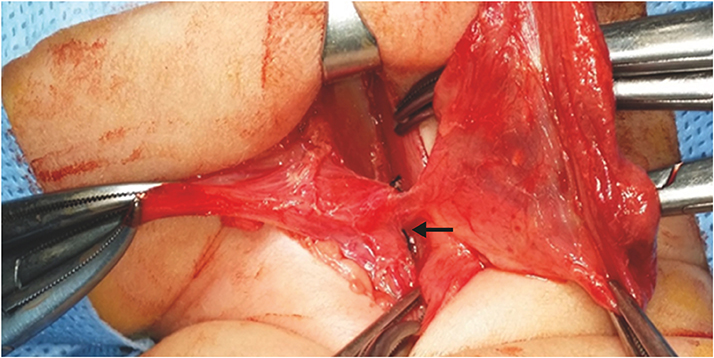

A newborn female infant, gestational age of 39+2 weeks, and 3.46 kg at birth was referred to our NICU due to a 7 cm sized left neck mass presented at birth. No significant medical history during antenatal care was noted. The baby arrived at our NICU 3 hours after birth and physical examination revealed a soft, tense, movable 7 cm long mass without signs of inflammation. Initial neck X-ray showed a 4.7×3.9 cm sized soft tissue density mass at left side of the neck containing round air density (Fig. 3A). With experience of patients with pyriform sinus cysts, gastric tube feeding was initiated from day 1. A sonographic study of the neck mass revealed findings consistent with pyriform sinus cyst, located at the medial side of the left carotid artery and extending to the posterior aspect of the left thyroid gland. The cyst was unilocular and contained isoechogenic debris. Esophagography showed a small tubular opacity from the left pyriform sinus adjacent to the air-filled cyst, suggesting a fistula (Fig. 3B). On neck magnetic resonance imaging (MRI), the fistula was not visualized but a cyst of homogeneous signal intensity without wall thickening or enhancement was visualized with air-fluid level, suggesting communication with the esophagus (Fig. 3C and D). On the 6th day of admission, pyriform sinus cyst resection and fistula ligation was done (Fig. 4). The size of the cyst was 7.0×3.5 cm on operation findings. Histological results of the dissected cyst were negative for malignancy and showed many benign squamous epithelial cells with some multinucleated histiocytes and mixed inflammatory cells. There was no intra-operative complication and the patient recovered uneventfully. Bottle feeding was initiated on postoperative day 7 and the patient was discharged 10 days after surgery.

Fig. 4

Surgical dissection of pyriform sinus cyst and fistula (black arrow) ligation was done.